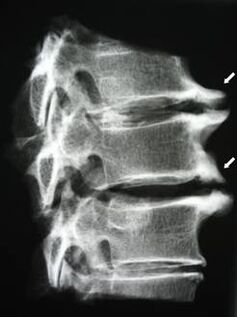

In the initial stages, osteochondrosis is detected using MRI.Later, the pathology can be diagnosed using radiography.On x-rays of the cervical spine, a reduction in the distance between the vertebrae, pathological changes in the facet joints and osteophytosis are noticeable.